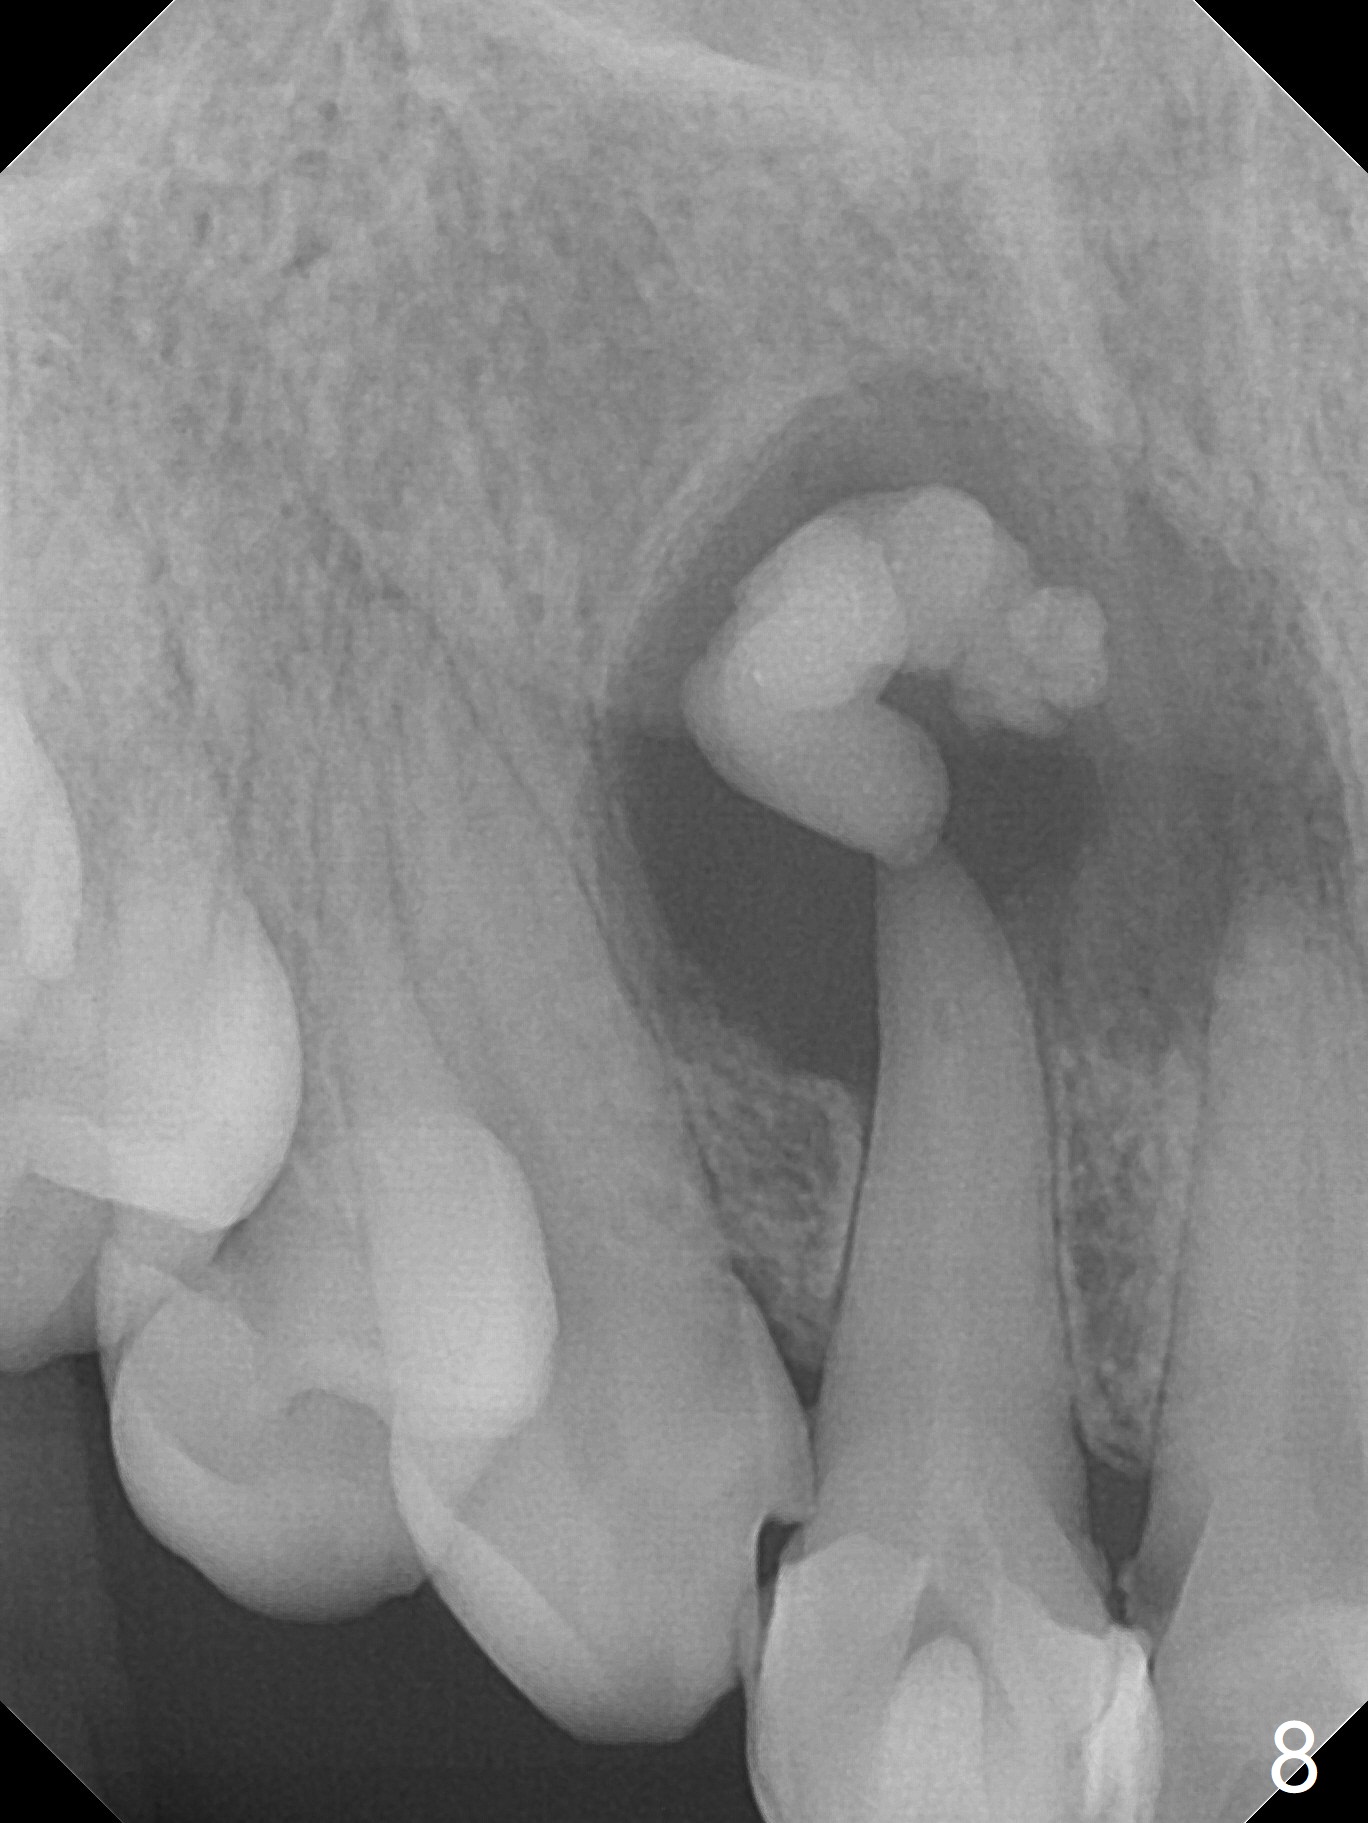

A 47-year-old woman (dental phobic) presented to clinic 9.5 years ago with periapical radiolucency (PARL) at #7 and 9 (Fig.1). RCT was done at #9 because of fistula and symptom 6 months later (Fig.2). While PARL increases at #7 without symptom, that at #9 disappears 8.5 years postop. Three months later, the patient returns for #7 RCT because of the abscesses (Fig.4 *) and pain. Intraop PA is taken with a 30/.06 rotary file in the canal with 19 mm working length (Fig.5). After use of #15 hand file for 20 mm, Ca(OH)2 paste is applied in the canal. When the rubber dam is removed, the abscesses enlarge (Fig.6), which may be related to sodium hypochlorite leakage. A dental explorer is used to try to find a bony opening to the large PARL without success (Fig.7). A postop PA reveals the leakage of Ca(OH)2 paste (Fig.8). Review of the preop PA (Fig.3,9) and intraop PAs (Fig.5,10) shows possible apical resorption and open apical foramen, which is the basis for the paste leakage (Fig.8,11). Careful analysis (with magnification and room light off) of pre- and intra-op PAs should be able to avoid use of #15 hand file out of apical constriction and the complication. The abscess has receded 1 month later (Fig.12). The paste has been resorbed 1 month later (Fig.13). A 30/.06 Gutta Percha is inserted at 18.5 mm (Fig.14 vs. 30/.06 file at 19 mm, 15 file at 20 mm last visit). Fig.15 is the final PA after closure of the access with composite (Fig.15).